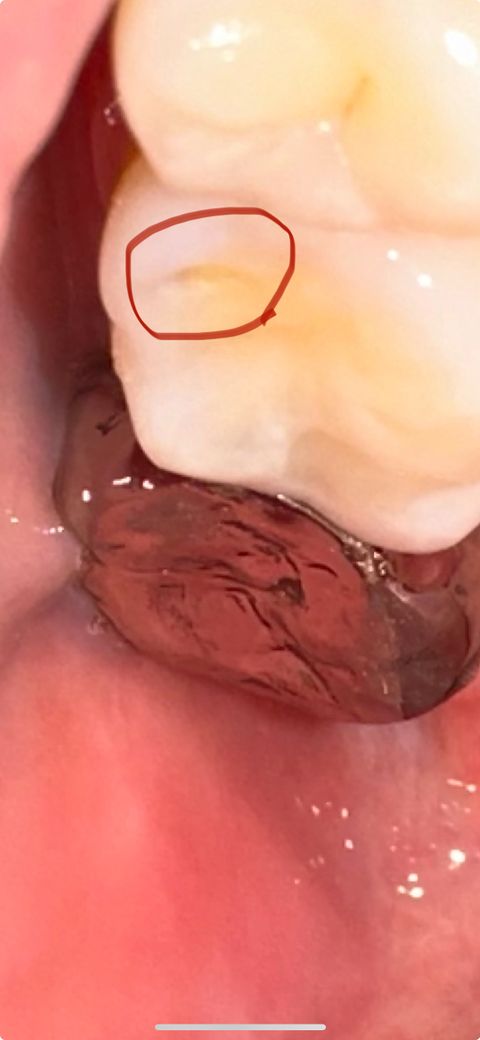

파인 정도가 심각한거일까요? ㅠㅠ 닳은거같아요

원래는 저런 구멍이 없었는데 생겼어요 근데 시간이 지나면 지날수록 더 깊숙이 들어가는것같고 더 파이는것같아요.. 치료가 급한거일까요? 아프거나 시리거나 하지는 않습니다 ㅜㅜ 가만히 놔두면 안되는거죠?

어금니에 해당 부위에 형태는 일반적으로 마모증이 발생했을 때 생기게 됩니다 마모증이 발생하게 되면 치아가 파절되어 해당 부위가 시들 수 있습니다 마모증이 발생되었다면 치아에 과도한 힘이 가해졌다는 의미이기 때문에 치아에 가해지는 힘을 줄여 주는 것이 좋습니다

치아가 마모되었거나 레진이 떨어진 것으로 보이며 간단하게 치료를 할 수 있을 것으로 보입니다.

안녕하세요 치과의사 김철진입니다. 예전에 레진치료를 받은곳이 떨어져 나간거 같습니다. 가셔서 다시 레진으로 치료를 하시면될것같습니다.

어금니가 마모되고 일부 떨어져 나간것 같습니다.

근본적인 치료는 크라운을 하시는게 되겠습니다.

불편한게 없으면 좀더 지켜보다가 추후에 크라운을 하시는게 어떨까 합니다.

현재 해당부위에 충치가 진행되고 있는 것으로 의심되기에 방치시 더 진행될수 있습니다. 따라서가능한 빠른시일내에 치과에 방문하여 상태확인후 치료를 받길 권합니다.